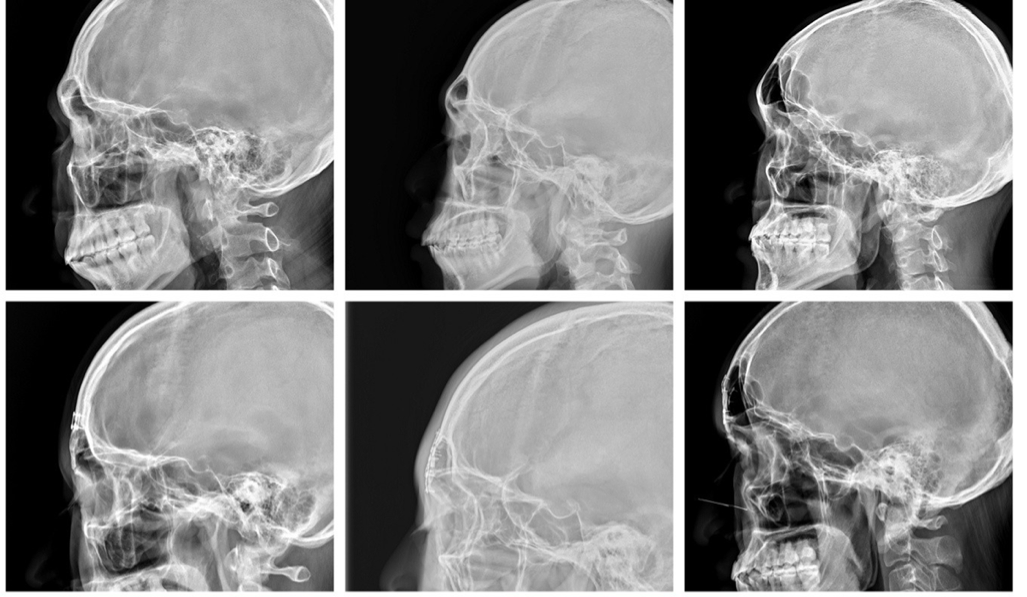

許多人都知道男性的額頭大多屬於第三型的額骨(額竇內有氣室的存在,突出的額竇伴隨兩側的突出的眼眶骨),但其實第三型的額骨仍然有進一步的分類:厚壁型、薄壁型及大氣室型。 厚壁型的個案數居中,通常指的是前額壁厚度大於3mm,處理上將前壁薄化合併前額氣室縮小,就可以達到不錯的美化效果。薄壁型的個案數最多,前額壁厚度在2mm上下,處理上不但要將前壁薄化外更要將前壁構形重新修整,再重新鋪整回去。大氣室型的個案數最少,不但前壁厚度偏薄而且氣室左右延伸兩顳側,處理的難度最高,構形的調整須同時考慮前額的切割範圍及結構調整。 第二代前額柔化手術跳脫過去的單純額頭厚推模式,對於薄壁型及大氣室型個案提供個製化構形修整,術後的結果均顯示出達到額頭柔化的效果(下圖)。

圖左: 厚壁型;圖中: 薄壁型;圖右: 大氣室型。